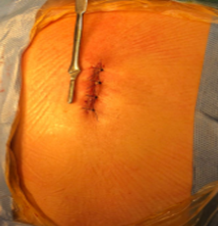

Las técnicas de mínima invasión ofrecen varias ventajas: incisiones pequeñas, menor riesgo de complicaciones, menor sangrado, menor agresión a los tejidos, rápida movilización y recuperación del paciente, generalmente el paciente puede ser dado de alta al día siguiente.